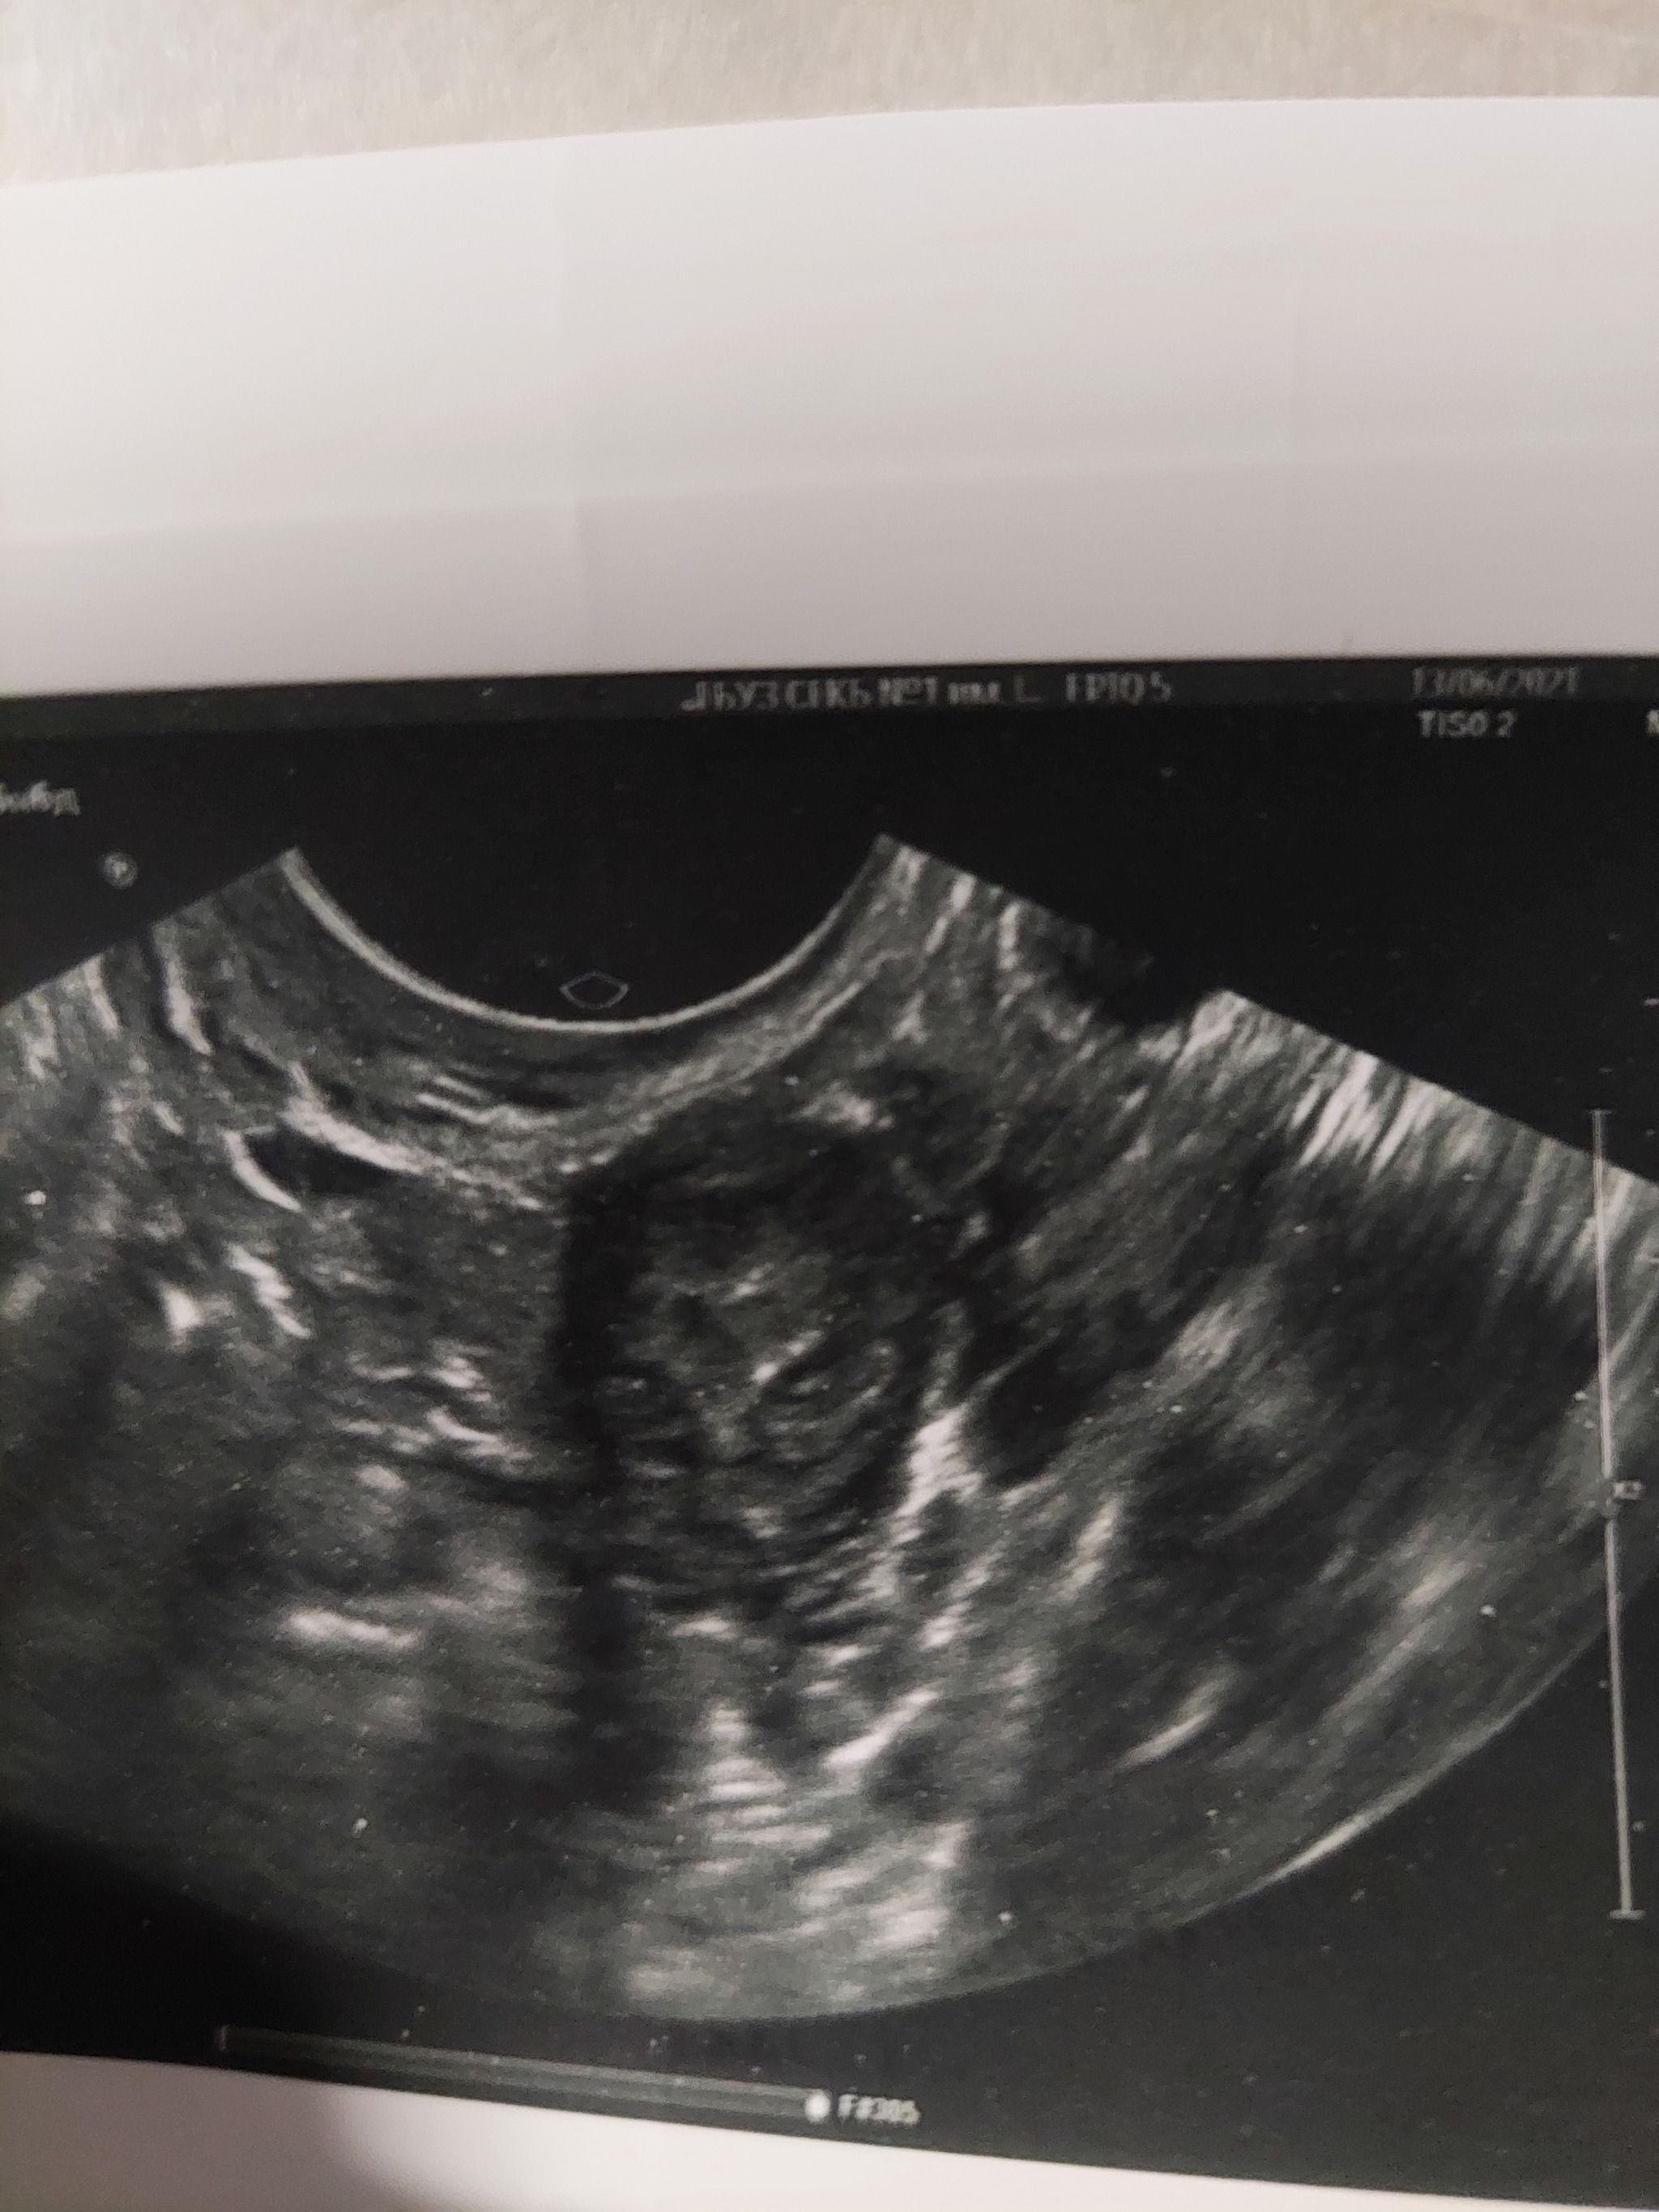

Работаю врачом УЗИ, при осмотре был найден яичник, с структурой в виде сердечка. А потом присмотрелся...это ж гуманоид:)